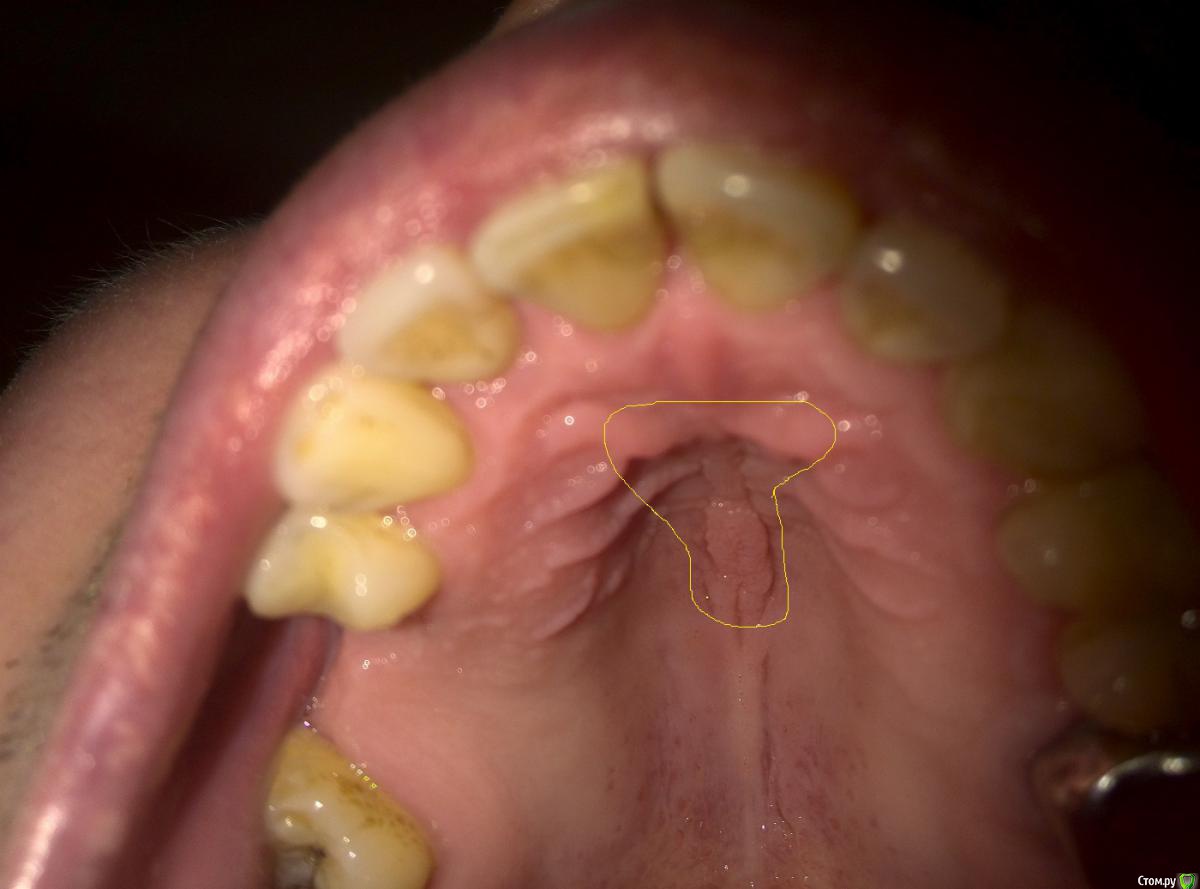

dddrive Опубликовано 23 марта, 2016 Поделиться Опубликовано 23 марта, 2016 Добрый день !Подскажите пожалуйста.В Декабре 2015 года появилось какое то жжение верху неба между передними зубами. Был как бы бугорок алый, стоматолог сказал что ничего страшного может травмировал чем то. Уже 3 месяц во рту не понятные ощущения ( как бы горит чтоли или как после ожога я бы сказал даже ) и не проходит. Что это может быть ? Сдал кучу анализом имуннограму ни чего не нашли. Как бы мешает все как опухло. P/S Сначала было как я уже писал возле передний зубов, а сейчас продвинулось как бы на середину твердого неба. На фото обвел область где беспокоит. Ссылка на комментарий